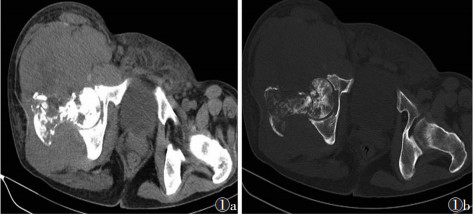

2.2 X线、CT表现8例行X线检查,6例呈溶骨型骨质破坏,表现为斑片状、片状溶骨型破坏,边界不清;2例呈混合型骨质破坏,表现为骨质破坏区内见斑片状密度增高影或病灶周围见硬化带(图 1a,1b)。5例病变周围见不同程度的软组织肿块,1例伴轻度层状骨膜反应。19例行CT检查中16例为溶骨型骨质破坏,3例混合型骨质破坏,15例病变骨周围见软组织肿块,1例合并病理性骨折伴出血,1例病灶内可见点状、小片状残存骨。3例骨皮质有轻度或无明显缺损,周围未见明确软组织肿块(图 2a,2b)。